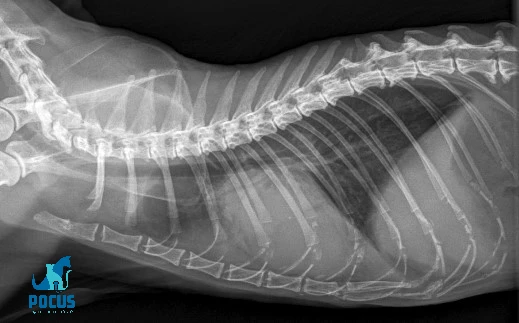

הסימנים הרדיוגרפיים למחלת לב וכשל לב בחתולים וכלבים